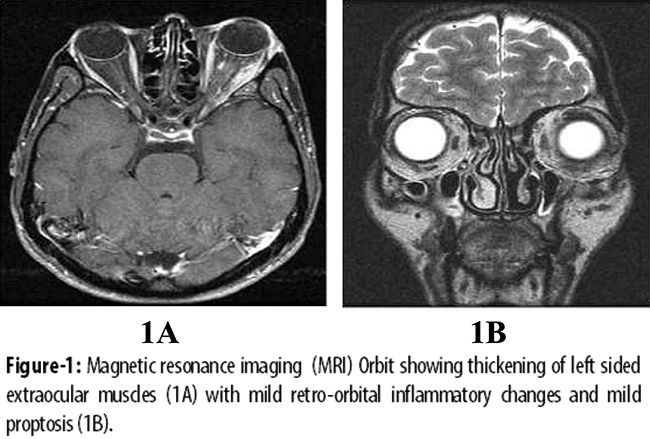

A 32-year-old male with history of asthma since childhood presented to our clinicin May 2012 with jaundice, epigastric pain andweight loss of 15kg over the preceding one year. General physical examination showed a protuberant left eye, which,according to the patient, was present for 12 years. Abdominal examination showed mild upper abdominal tenderness. He had sought prior medical consultation at another hospital where a computed tomography (CT) scan of abdomen was performed which revealed a dilated common bile duct (CBD), intra-hepatic duct (IHD)dilatation and a mass in the pancreatic head. Endoscopic retrograde cholangio-pancreatography (ERCP), performed about 10 months earlier, showed a distal CBD stricture for which a biliary stent was placed. The bilirubin levels had gradually decreased thereafter over a period of six months. A magnetic resonance cholangiopancreatography (MRCP) performed in our centre at the time of presentation, redemonstrated the pancreatic head mass measuring 2.2cm x 2.1cm, a distal CBD stricture and kinking of the distal pancreatic duct. Laboratory investigations showed a normal complete blood count (CBC) and deranged liver function tests (LFTs) with total bilirubinof 0.41 mg/dl, direct bilirubin 0.20mg/dl, alkaline phosphatase 774 U/L, gamma glutamyltranspeptidase 346 U/L, aspartate aminotransferase (AST) 56 U/L and alanine aminotransferase (ALT) 51U/L. ERCP was then performed for cholestatic LFTs. The previously placed plastic stent was removed, and the cholangiogramobtained showed an irregular CBD with two strictures, one in distal CBD and another in the proximal portion which extended into the right IHD. Two stents were placed, one each in the left and right ductal systems. Esophagogastroduodenoscopy and colonoscopy showed normal mucosa and histopathology revealed normal duodenal and colonic biopsies. Serological workup showed an elevated IgG value of 48.3G/L (reference range: 7.2-15.8 gm/L) with IgG4 level of 7.5 gm/L(reference range: 0.1-1.3gm/L). The level of CA 19-9 was normal i.e. 8.93 U/ml (routine: <33U/ml). The anti-nuclear antibody was weakly positive at a titer of 1:40, while the anti-smooth muscle antibody, anti-mitochondrial antibody and anti-liver kidney microsomal antibody were all negative. The viral serology, including hepatitis B surface antigen (HBsAg) and anti-hepatitis C antibodies (anti-HCV)were non-reactive. Liver biopsy showed minimally expanded portal tracts with lymphocytic infiltrate, fibrosis, occasional foci of lobulitis, mild focal cholestasis and no piecemeal necrosis. The modified histology activity index (HAI) stage was 2/6. The thyroid function tests were all normal but anti-thyroid peroxidase antibody level was found to be abnormally high i.e. 90.2 IU/ml (cut off <35 IU/ml). Thyroid scan showed normal uptake of radiocontrast. Anti-neutrophil cytoplasmic antibodies (ANCA), includingc-ANCA and p-ANCA, were negative. Magnetic resonance imaging (MRI) of the orbit showed thickening of all left-sided extra-ocular muscles, predominantly left lateral rectus and inferior rectus muscles with mild retro-orbital inflammatory changes and mild proptosis, consistent with orbital inflammatory pseudotumour (Figure-1).